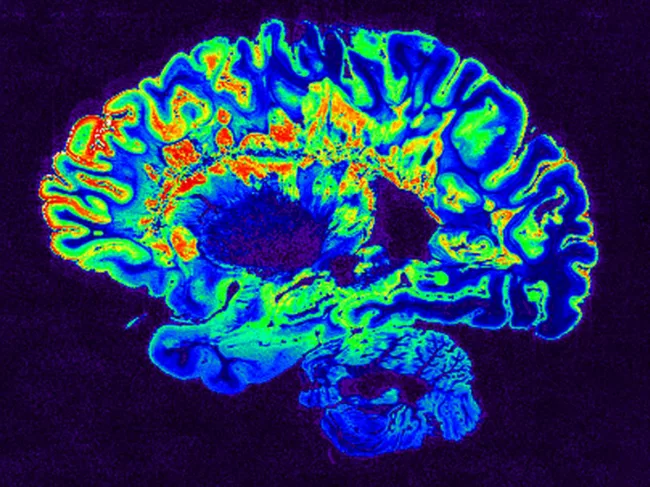

MRI scan of a fixed cerebral hemisphere from a person with multiple sclerosis

First GWAS for MS severity turns up first brain-related SNP

Multiple sclerosis (MS) is and remains “a problem in the immune system” Stephen Sawcer told BioWorld. As in other autoimmune diseases, a faulty immune system attacks otherwise healthy tissues that it should be leaving alone. In the case of MS, the tissue in question is oligodendrocytes. And a study published online in Nature on June 28, 2023, suggests that while MS’ beginnings are autoimmune, the path it takes in an individual patient is determined in part by how well the brain can cope with the autoimmune attack. Read More